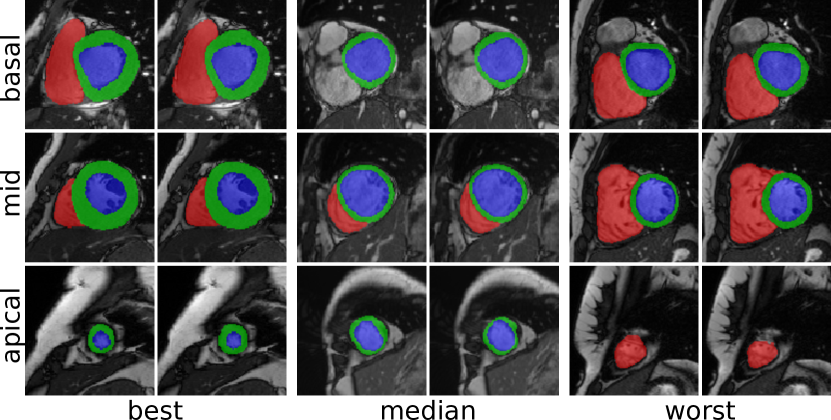

Clinical measures for the best performing method (the modified 2D U-Net) are shown in Table 3. A detailed description of the measures is provided by ACDC3. Figure 1 shows example segmentation results at three slice positions using the above method. Inference on a single volume took approximately 1.1 for the 2D networks and 2.2 for the 3D networks using a Nvidia Titan Xp GPU.